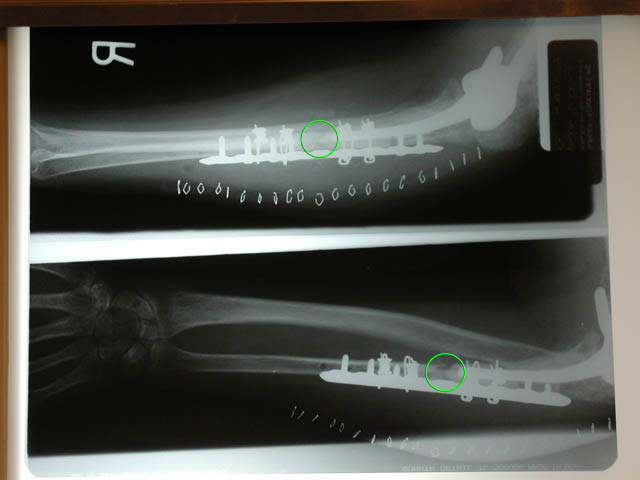

Marla's X-Rays show the repairs that Dr. Sachar performed on Marla's ulnar bone during her surgery on 12/8/2004. The green circles show where her ulna is broken. Dr. Sachar stabilized the bone by embedding a new plate, performing a bone graft in in the break, and utilizing a cadaverous fibula to provide support.

The incision for December's surgery followed the same scar as previous surgeries. Shown are the staples holding the wound closed.